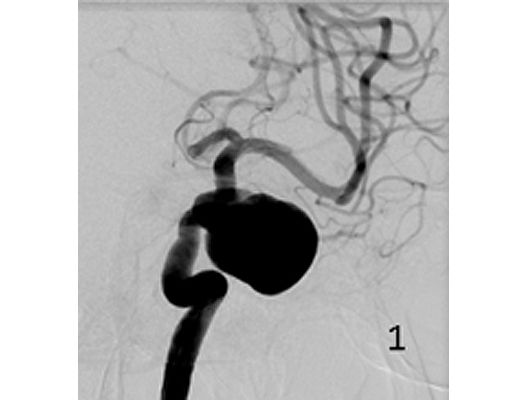

Das Beispiel zeigt die angiographischen Bilder einer Patientin, bei der es zu einer Sehstörung gekommen war. Die Ursache war ein großes Aneurysma der Halsschlagader an der Schädelbasis (Bild 1). Bild 2 zeigt die Lage des Aneurysmas hinter dem Auge. Durch den Druck des Aneurysmas auf den Sehnerv war es zu der Sehstörung gekommen. Die Patientin wurde mit einer speziellen Gefäßprothese versorgt, welche über eine Punktion der Leistenarterie in die Halsschlagader eingesetzt wurde (Bild 3). Bei der Kontrolle nach 6 Monaten zeigte sich ein vollständiger Verschluss des Aneurysmas (Bild 4). Die Sehstörung hatte sich vollständig zurückgebildet.